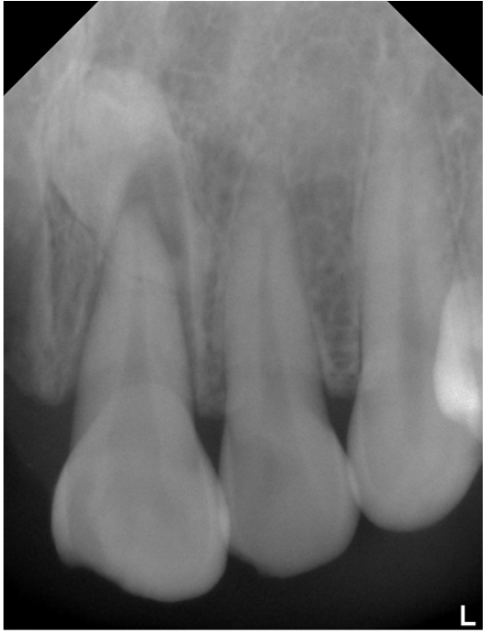

55.2.依下圖口內彩色照片,及X光咬合片影像,下列何種診斷正確?

(A)口底腫瘤 (B)唾液結石堵塞於Stensen’s duct (C)唾液結石堵塞於Wharton’s duct (D)此問題是由舌下腺引起的

56.3.該患者應如何處置?①將口底紅腫塊切除 ②將堵塞之黃白硬塊,以牙科檢查用之forceps 反夾後,在其表面黏膜切開擠出硬塊即可 ③給予抗生素 ④鼓勵術後多喝水 (A)①③④ (B)只有②③ (C)只有③④ (D)②③④